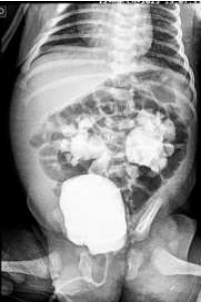

A UCM foi realizada, e uma das imagens encontra-se abaixo:

II. A imagem da UCM evidencia achados típicos de válvula de uretra posterior.